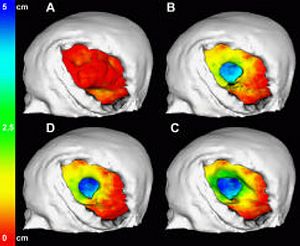

MRI with labeled structures from atlas registered to the CBCT. Registration was carried out with the open source imaging tool 3D Slicer, Version 4.4.0. |